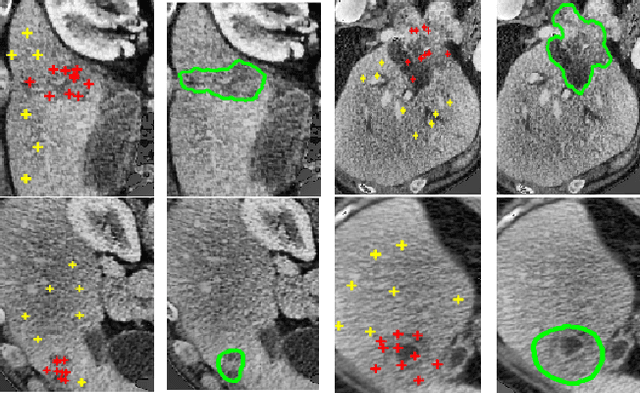

Abstract:Lesion segmentation is an important problem in computer-assisted diagnosis that remains challenging due to the prevalence of low contrast, irregular boundaries that are unamenable to shape priors. We introduce Deep Active Lesion Segmentation (DALS), a fully automated segmentation framework for that leverages the powerful nonlinear feature extraction abilities of fully Convolutional Neural Networks (CNNs) and the precise boundary delineation abilities of Active Contour Models (ACMs). Our DALS framework benefits from an improved level-set ACM formulation with a per-pixel-parameterized energy functional and a novel multiscale encoder-decoder CNN that learns an initialization probability map along with parameter maps for the ACM. We evaluate our lesion segmentation model on a new Multiorgan Lesion Segmentation (MLS) dataset that contains images of various organs, including brain, liver, and lung, across different imaging modalities---MR and CT. Our results demonstrate favorable performance compared to competing methods, especially for small training datasets.

Abstract:We propose a fully-automated method for accurate and robust detection and segmentation of potentially cancerous lesions found in the liver and in lymph nodes. The process is performed in three steps, including organ detection, lesion detection and lesion segmentation. Our method applies machine learning techniques such as marginal space learning and convolutional neural networks, as well as active contour models. The method proves to be robust in its handling of extremely high lesion diversity. We tested our method on volumetric computed tomography (CT) images, including 42 volumes containing liver lesions and 86 volumes containing 595 pathological lymph nodes. Preliminary results under 10-fold cross validation show that for both the liver lesions and the lymph nodes, a total detection sensitivity of 0.53 and average Dice score of $0.71 \pm 0.15$ for segmentation were obtained.

Abstract:We propose a novel method, the adaptive local window, for improving level set segmentation technique. The window is estimated separately for each contour point, over iterations of the segmentation process, and for each individual object. Our method considers the object scale, the spatial texture, and changes of the energy functional over iterations. Global and local statistics are considered by calculating several gray level co-occurrence matrices. We demonstrate the capabilities of the method in the domain of medical imaging for segmenting 233 images with liver lesions. To illustrate the strength of our method, those images were obtained by either Computed Tomography or Magnetic Resonance Imaging. Moreover, we analyzed images using three different energy models. We compare our method to a global level set segmentation and to local framework that uses predefined fixed-size square windows. The results indicate that our proposed method outperforms the other methods in terms of agreement with the manual marking and dependence on contour initialization or the energy model used. In case of complex lesions, such as low contrast lesions, heterogeneous lesions, or lesions with a noisy background, our method shows significantly better segmentation with an improvement of 0.25+- 0.13 in Dice similarity coefficient, compared with state of the art fixed-size local windows (Wilcoxon, p < 0.001).